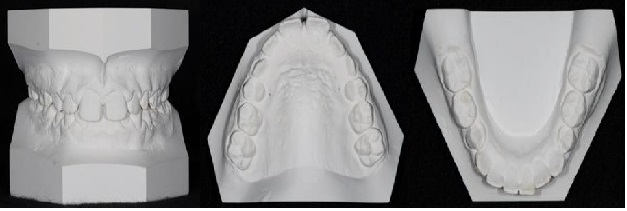

• studio sui modelli in gesso delle arcate dentali (Fig.2)

Fig.2.modelli studio in gesso